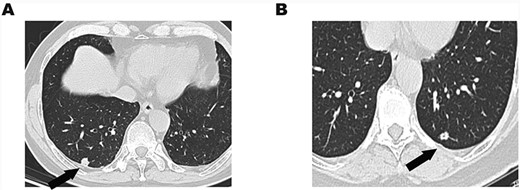

(A) Chest CT showed an 11-mm solitary nodule with central cavity in the right S10 segment. (B) An 8.5-mm solitary nodule with central cavity in the left S10 segment.

A 64-year-old woman was admitted to our hospital due to a gradually enlarged nodule in the left S10 segment. The nodule was about 5 mm when it was first found in 2007. It became 8.5 mm in 2019 (Fig. 1B). She insisted on receiving wedge resection instead of lobectomy even if the nodule was malignant. The intraoperative frozen examination indicated adenocarcinoma, and there is no further operation for her.